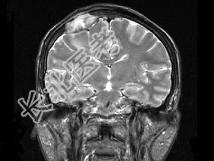

单项选择题男,63岁, 反复抽搐30余年加重伴左侧肢体活动不利活1月余,PE: 右顶部约4cm×5cm大小隆起包块质硬,不能活动, 右上下肢肌力Ⅴ,左上下肢肌力Ⅳ+, 根据所提供图像,最可能的诊断为 ( )

A、右顶骨(副脊索瘤)或称为肌上皮瘤

B、右顶骨转移瘤

C、右顶骨骨瘤

D、右顶骨血管瘤

E、右顶骨胆脂瘤